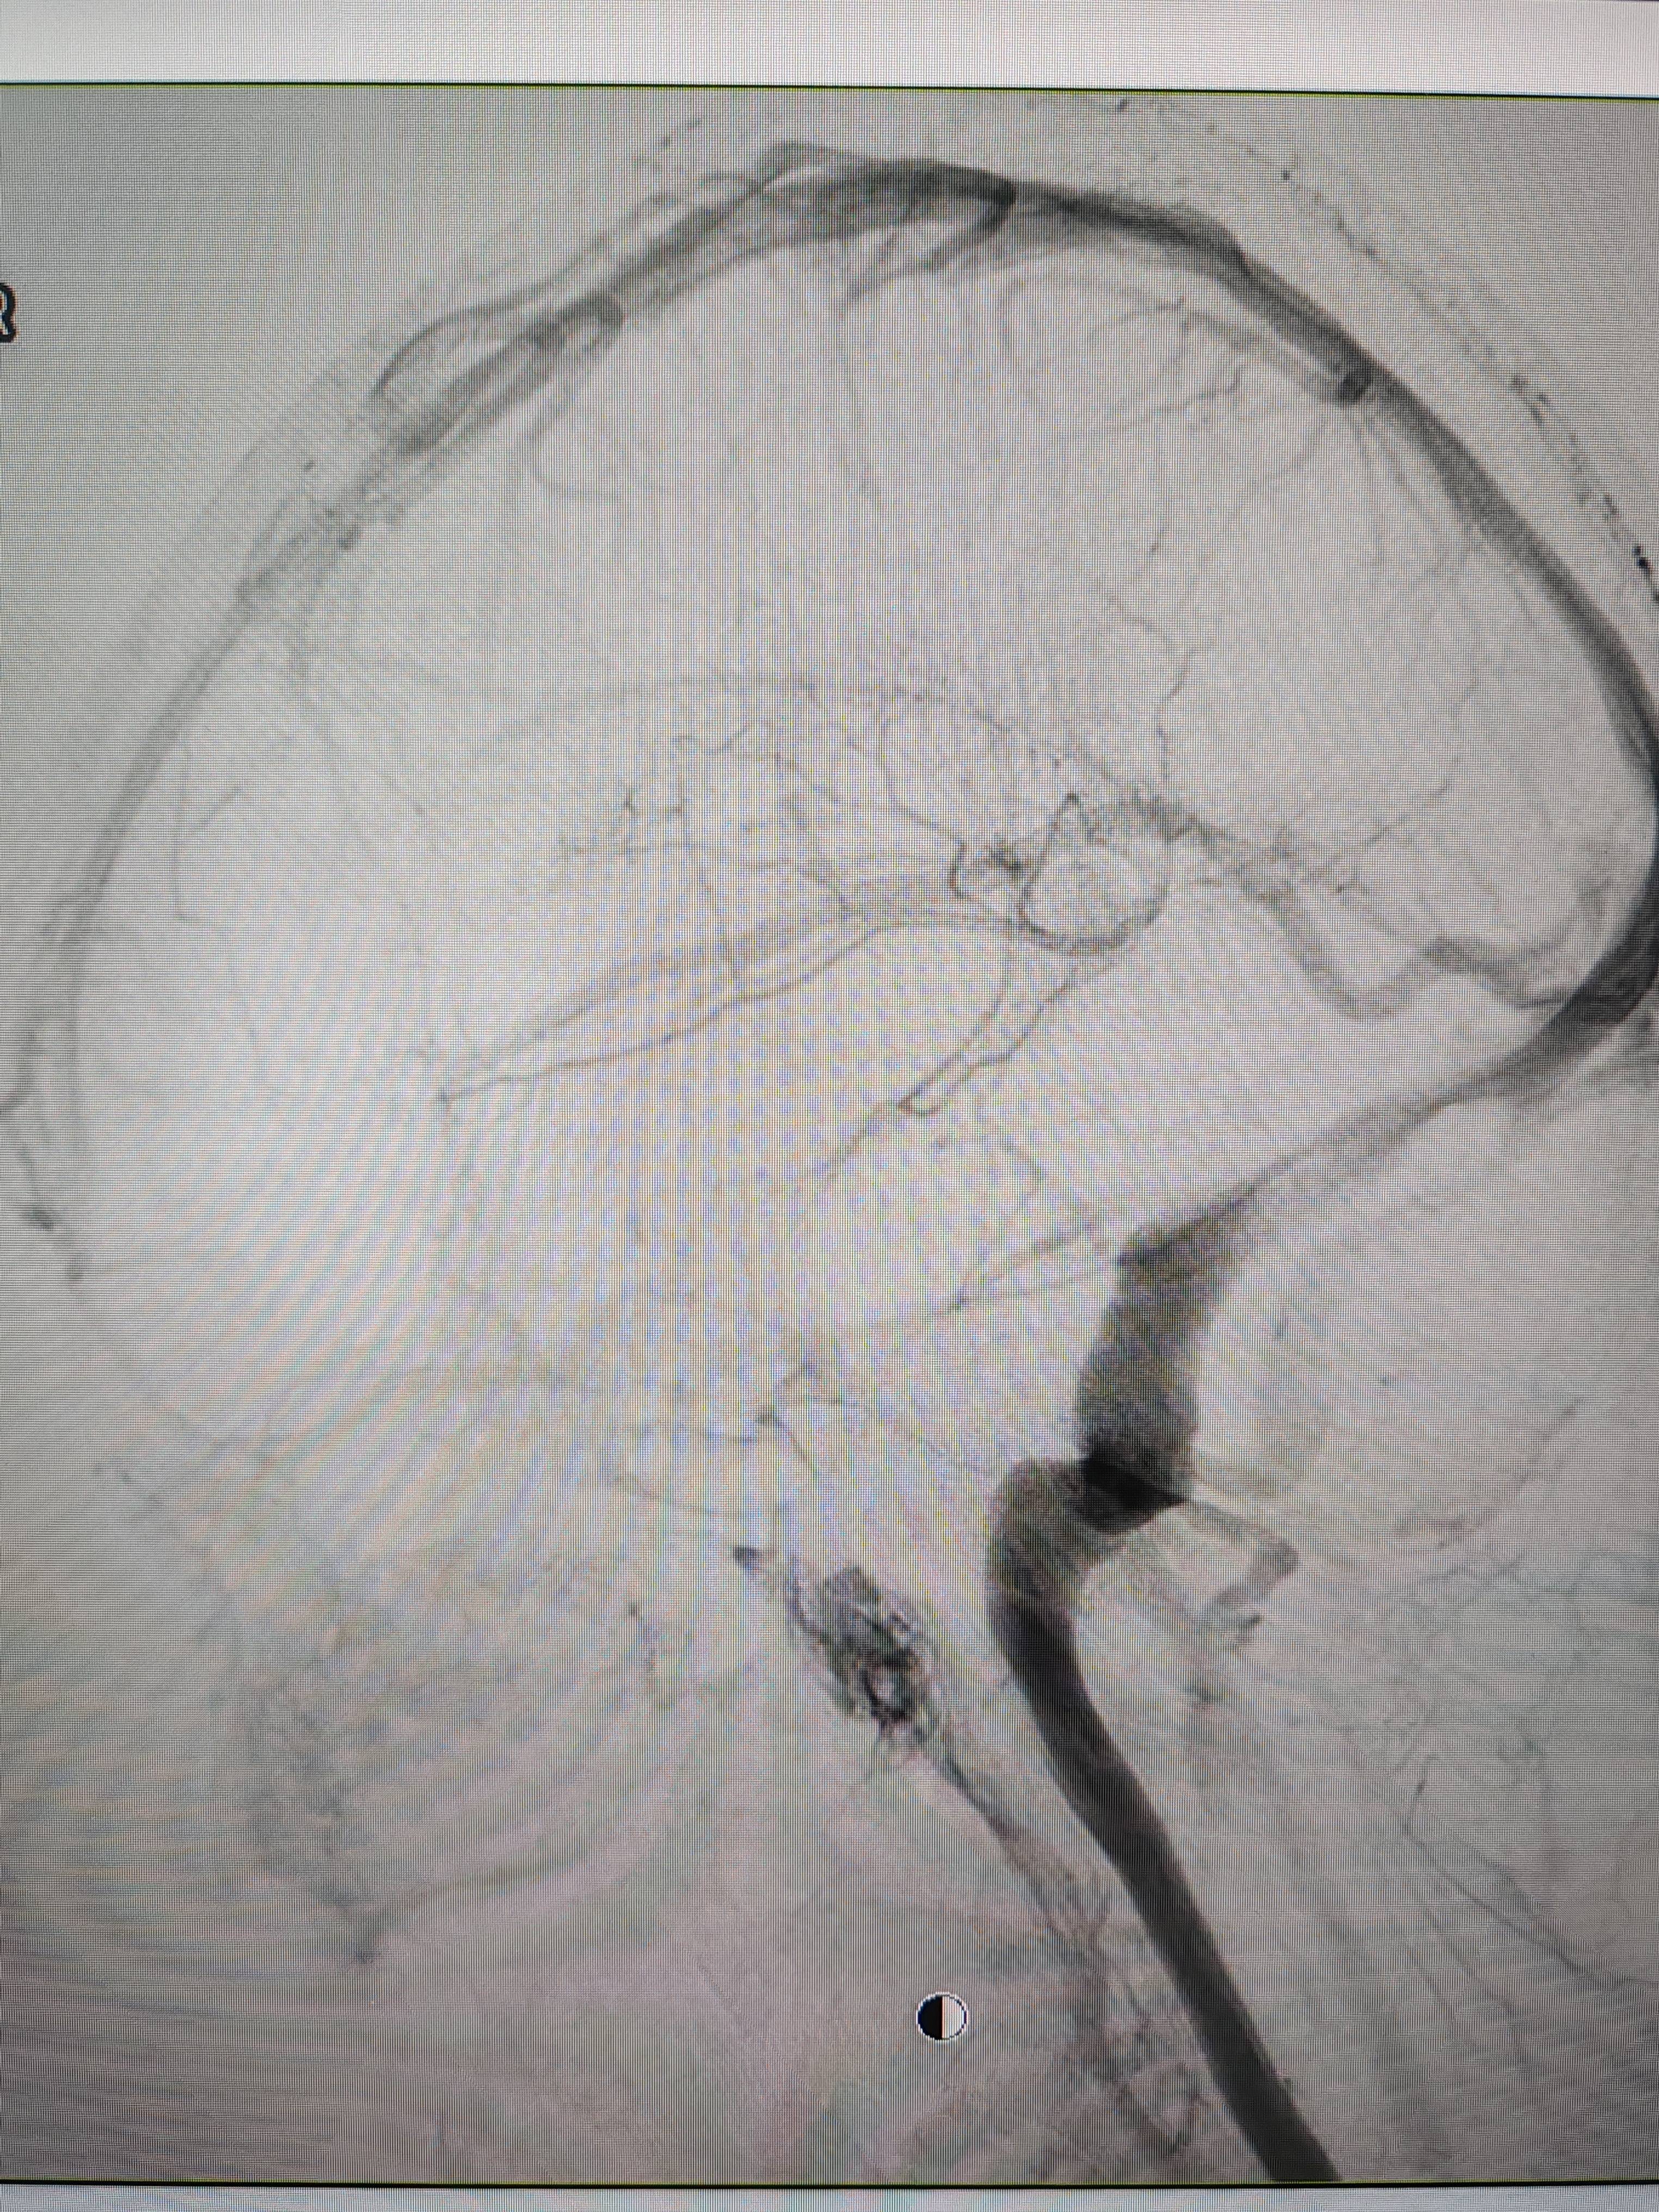

患者造影图像显示,其耳侧静脉窦狭窄理财学。 南方+ 欧阳少伟 拍摄

李宝民举例说,通过查体、CT、造影等影像技术的检查,患者赵女士是由于静脉窦狭窄,导致缓慢的静脉血流也出现“湍流”现象,其拐弯、打漩涡、回流产生的声响,又顺着骨传导,传至耳蜗处,进而让患者出现搏动性耳鸣的症状理财学。